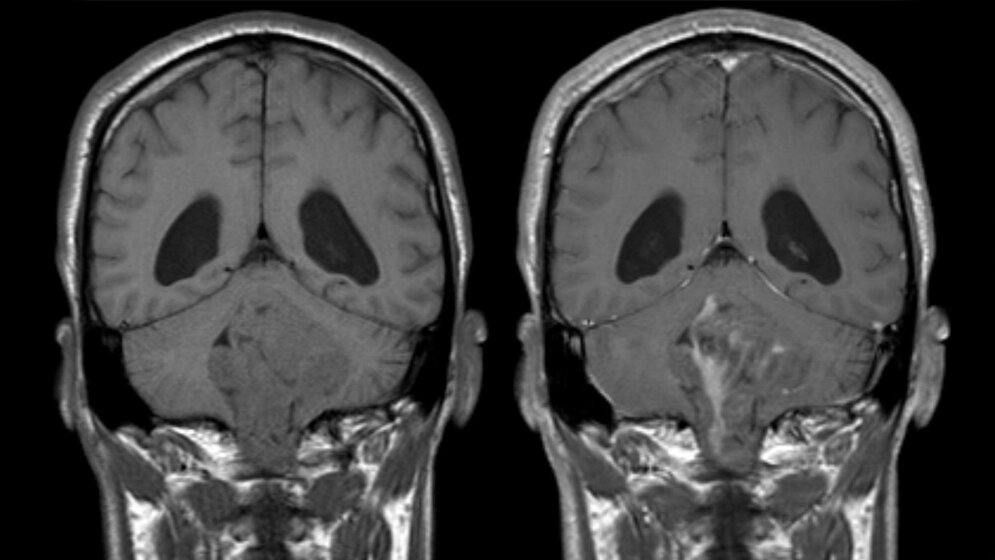

Bisher stand Ärzten zur Einteilung von Ependymomen die histopathologische Untersuchung zur Verfügung, die jedoch keine zuverlässigen Aussagen über Verlauf und Biologie der Erkrankung zulässt. Mit dem Ziel, die Tumoren genauer zu klassifizieren, bestimmten Dr. Kristian Pajtler, PD Dr. Hendrik Witt und Dr. Marcel Kool am DKFZ gemeinsam mit einer großen Gruppe nationaler und internationaler Kooperationspartner die epigenetischen Muster von über 500 Ependymomen. „Durch den Vergleich dieser Muster konnten wir insgesamt neun verschiedene Untergruppen von Ependymomen unterscheiden. Zwei dieser Gruppen umfassten vor allem Kinder mit einem hohen Rückfallrisiko und schlechter Prognose“, erklärt PD Dr. Hendrik Witt. „Insgesamt waren die Gruppenunterschiede jedoch bei allen neun Gruppen groß, und zwar nicht nur hinsichtlich der Epigenetik, sondern auch in den DNA-Codes der jeweiligen Tumoren, ihrer Genaktivität, dem Erkrankungsalter der jeweiligen Patienten und dem Krankheitsverlauf.“ Da die epigenetischen Muster im Verlauf der Erkrankung stabil bleiben und schon winzigste Probenmengen für die Bestimmung ausreichen, eignen sie sich gut für die klinische Routinediagnostik.